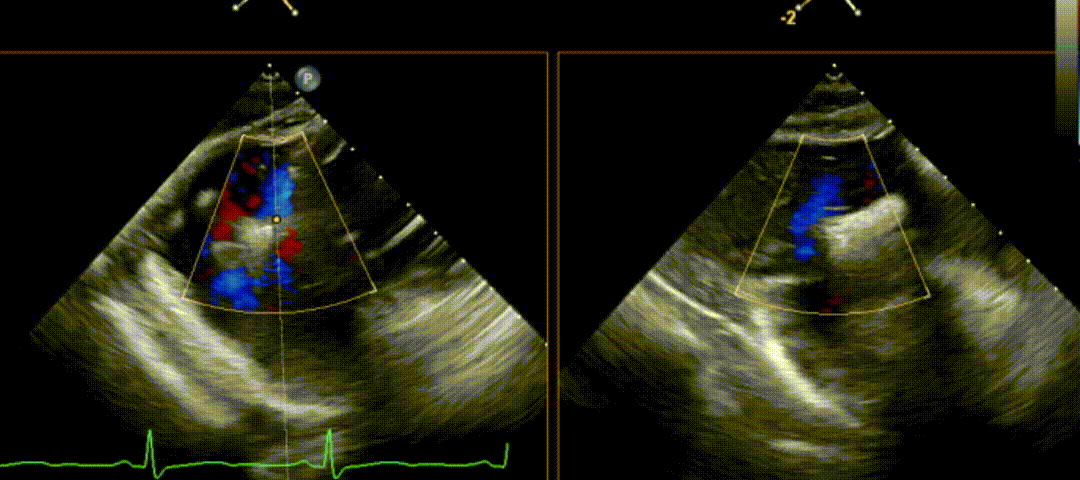

第二枚三尖瓣夹释放后,残余反流由术前4+降至微量,患者平均跨瓣压差仅为1mmHg。经评估,患者反流改善效果明显,三尖瓣夹稳定。手术过程、结果令人满意。

术后X-plane(上彩)

术后胃底(上彩)